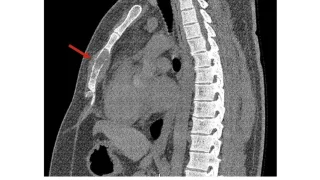

手術日+728日目 2026/2/25(水)(筋肉内神経鞘腫)